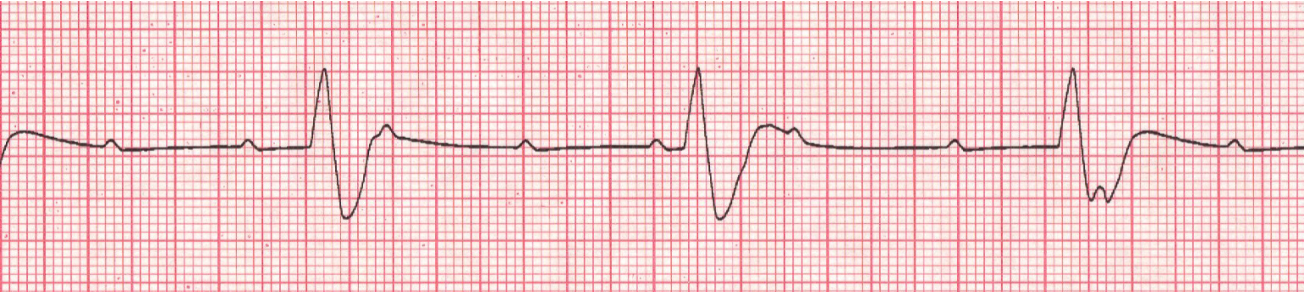

Premature Ventricular Complexes (PVCS)

key feature: early ventricular beat for irritable focus (sends out a signal before it is supposed to) → heart has less time to fill with blood → weak beat → ↓ amt of total volume being pumped to the rest of the body aka ↓ CO